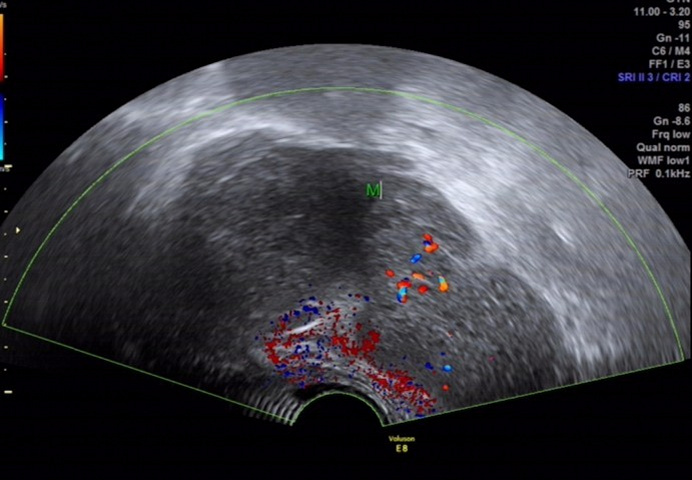

超声所见

骶尾部皮下软组织层内探及一范围约 145×98×107mm 的低回声包块,围绕骶骨生长,部分向盆腔内生长,与周围其他组织分界清楚,内部回声欠均匀, CDFI:内见多个条状血流信号, PW 检测:呈动脉频谱, RI:0.72 。

图 2 用凸阵探头经骶尾部扫查见包块围绕骶骨生长,并与骶骨分界不清

图 3 CDFI:包块内见多个条状血流信号